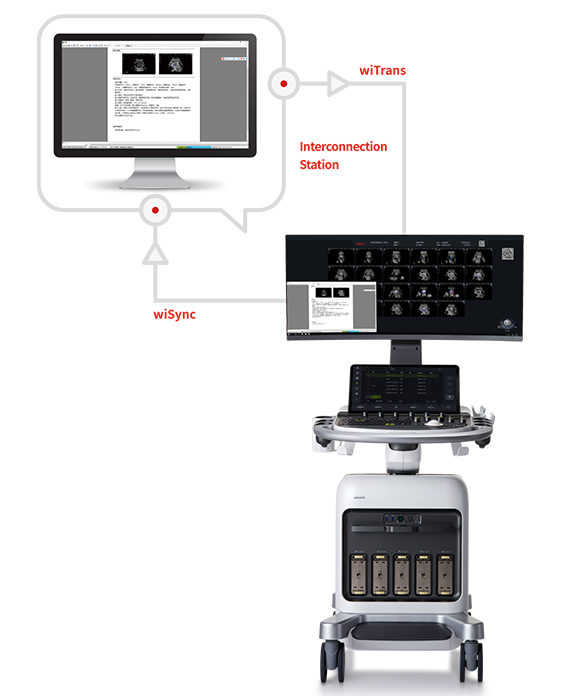

Conceptions ergonomiques et flux de travail d'IA efficace, offrant une expérience utilisateur extraordinaire